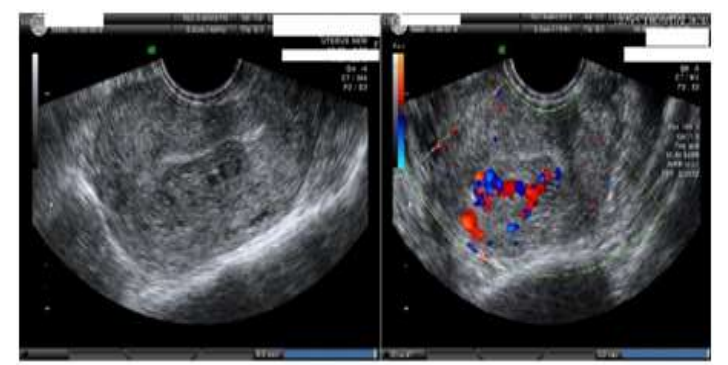

Shintre and Coelho [16] reported a 27-year-old lady who was known to have Thalassemia minor who had manifested with heavy vaginal bleeding and passage of clots over the preceding two days. She stated that she had been having continuous on and off mild to moderate vaginal bleeding pursuant to a second trimester therapeutic abortion she had undergone two months preceding her presentation. She did undergo therapeutic abortion in view of the fact that she had her chorionic venous samples which had shown that the foetus had Thalassemia major due to the fact that both herself and her husband had Thalassemia minor. The therapeutic abortion was induced with utilization of misoprostol (PGE1) tablets. The reports of the obstetrician who undertook the therapeutic abortion did document that the abortion was complete and therefore no curettage was undertaken pursuant to her abortion. She had also undergone another therapeutic abortion 8 months earlier for the same reason following chorionic villous sampling that showed Thalassemia major foetus. This therapeutic abortion was ensued by curettage of her uterine cavity for complete evacuation of her products of conception. She did not have any significant past medical or surgical history. She was noted to be pale or otherwise her general examination was normal. She had speculum examination of her vagina which showed a partially open cervical os that associated with minimal blood clots. There was no active bleeding. Her uterus was bulky, and it measured about 8 weeks to 10 weeks size as well as it was firm to soft in consistency, firm to soft with regard to consistency, mobile and associated with free fornices. The results of some of his laboratory blood tests included: Haemoglobin 9.5 grams per decilitre, platelets 3-lakhs, Serum Beta Human Chorionic Gonadotrophin (B-HCG) 35 MIU/ML which was normal, normal coagulation screen and normal liver function tests. Her blood sample was sent for grouping and saving for future use when required. She had ultrasound scan and magnetic resonance imaging (MRI) of pelvis. The MRI scan demonstrated a bulky uterus that measured 4 cm x 7 cm x 7 cm, heterogeneous lesion within the posterior wall of her uterus, lost endometrial-myometrial interface, multiple dilated tortuous blood vessels within her posterior myometrium which had suggested the likelihood of retained products of conception or gestational trophoblastic tumour which would represent placental site trophoblastic tumour, or uterine vascular malformation (see figure 1). The trans-abdominal ultrasound scan of pelvis did demonstrate an 8.8 cm x 7.5 cm x 7.5 cm bulky uterus the posterior myometrium that was very enlarged as well as heterogeneous with increased vascularity upon Doppler ultrasound scanning (see figure 2). Doppler ultrasound scanning did demonstrate a peak systolic velocity (PSV) of 121 cm / s as well as restrictive index of 0.36. The ultrasound scan also demonstrated that her endometrium was thickened within the lower uterine segment that was suggestive of retained products of conception. She had a chest x-ray which was normal. She had ultrasound scan-guided evacuation of her retained products of conception from her lower uterine segment which was sent for pathology examination. The evacuation of the products of conception did trigger active bleeding. She therefore underwent uterine artery embolization with utilization of cyanoacrylate (glue) (see figure 3). There was no evidence of active bleeding pursuant to her embolization. She was discharged on the 3rd post-procedure op day on oral antibiotics and haematinics. Pathology examination of the tissue did show degenerated and necrosed bits of decidua as well as few degenerate chorionic villi that were admixed with fibrin and blood. The degenerate products of conception did not show pathology examination features of placental site tumour trophoblastic. At her 6-weeks follow-up assessment she stated that her vaginal bleeding had diminished gradually over a period of 4 weeks and the bleeding stopped completely after 4 weeks. She had ultrasound scan of her pelvis with Doppler scan which did show diminished size of the arteriovenous fistula and with diminished vascularity (see figure 4). Shintre et al. [16] stated that the first case of AVM of the uterus was reported in 1926. [17]

Figure 2: USG-pelvis revealed 8.8 cm x 7.5 cm x 7.5 cm bulky uterus the posterior myometrium markedly enlarged and heterogeneous with increased vascularity on Doppler. Doppler showed PSV of 121 cm / s & RI of 0.36 i.e., high velocity, low resistance flow, ET-14mm in lower uterine segment. Reproduced from: [16] Shintre H S, Coelho K S. Managing Uterine Arteriovenous Malformation (AVM) Is Like Dealing with Raging Wildfire Awaiting A Spark: Better Be Extremely Cautious & Be Ready With Counter Measures Like Uterine Artery Embolization (UAE). Obstet. Gynecol. Int. J. 2017; 6(1): 00195 DOI: 10.15406/ogij:2017.06.00195

https://medcraveonline.com/OGIJ/managing-uterine-arteriovenous-malformation-avm-is-like-dealing-with-raging-wildfire-awaiting-a-spark-better-be-extremely-cautious-amp-be-ready-with-countermeasures-like-uterine-artery-embolization-uae.html under copy right ©2017 Shintre, et al. This is an open access article distributed under the terms of the, which permits unrestricted use, distribution, and build upon your work non-commercially